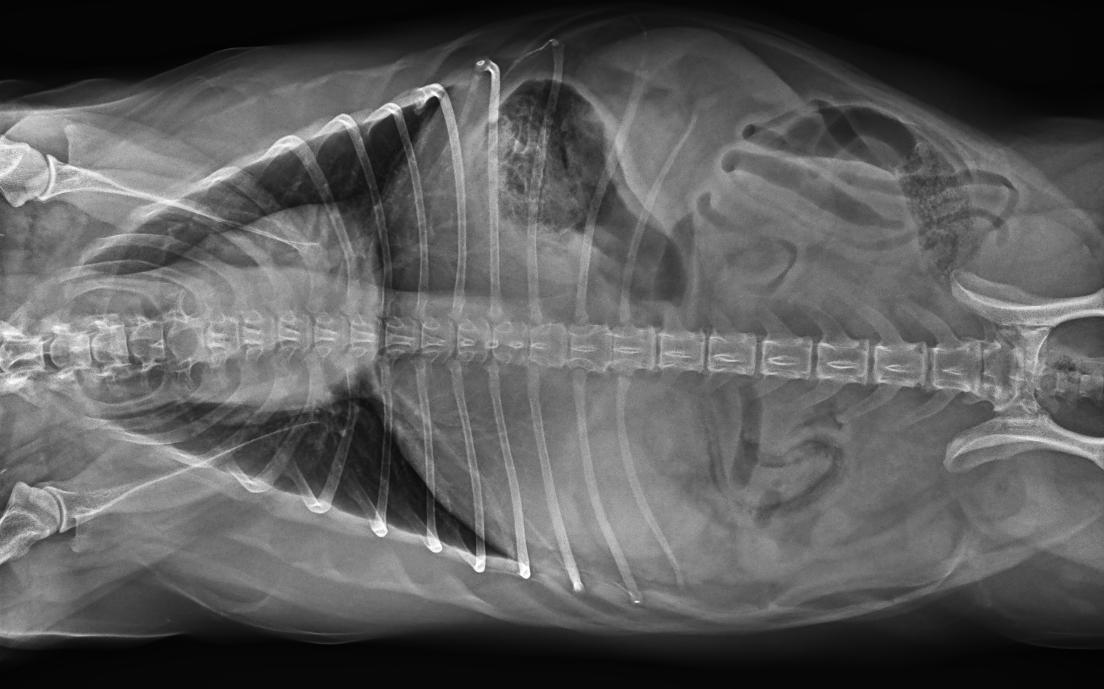

● 17*17大尺寸平板探測(cè)器,獲得高質(zhì)量圖像

● 優(yōu)異的空間分辨率及信噪比,提升圖像質(zhì)量

● 采用線噪聲消除技術(shù),使成像質(zhì)量提升40%

● 進(jìn)口高品質(zhì)球管,大功率、高熱容量、微焦點(diǎn),1.0/2.0mm雙焦點(diǎn)設(shè)計(jì)

● 25kHz高主逆變頻率,輸出電壓更穩(wěn)定;瞬時(shí)定格影像,無(wú)拖尾現(xiàn)象

● 智能高效的圖像處理軟件,大幅提升圖像質(zhì)量